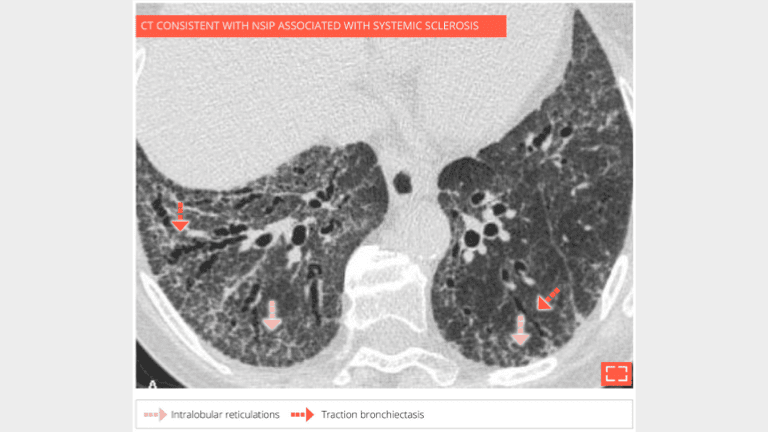

Diffuse ground-glass opacities in the lower posterior lungs with intralobular reticulations and traction bronchiectasis, no honeycombing.

2. Intralobular reticulations

Intralobular reticulations

Marked intralobular reticulations in the 2 lung bases without honeycombing. Note the relative lung savings immediately under pleura, pointing to a NSIP.